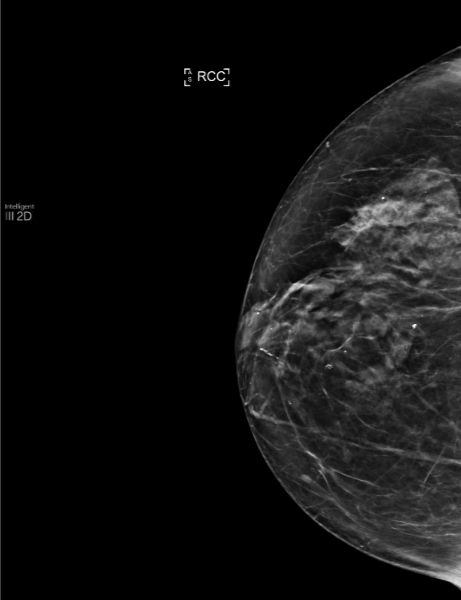

Cas de la semaine (semaine 50, 2024)

Bilan annuel après tumorectomie du sein gauche.

Le radiologue est alerté par MammoScreen qui pointe une lésion prépectorale G et la classe à un score de 7. Cette masse était déjà présente sur les deux précédentes mammographies, interprétée comme un ganglion. Suite au résultat de l’IA, le radiologue examine la lésion en tomosynthèse et découvre des contours microspiculés, ainsi qu’une petite augmentation de volume comparativement à la mammographie précédente. L’échographie retrouve une masse ACR4 et la biopsie révèle un CCI SBRI.

Ce dossier illustre le risque de méconnaissance de certains cancers lentement évolutifs, initialement de morphologie bénigne, dont l’aspect peu inquiétant et l’ancienneté n’alerte pas le radiologue. L’IA, contrairement à l’humain, reste vigilante sur toutes les données tomosynthèse, et a permis dans ce dossier d’alerter à juste titre le radiologue.

A noter que les performances sur des seins opérés n’ont pas été établies. MammoScreen n’est pas réglementairement approuvé pour une utilisation sur ce type de cas.

Imagerie Médicale Mermoz (Dr Tourasse)